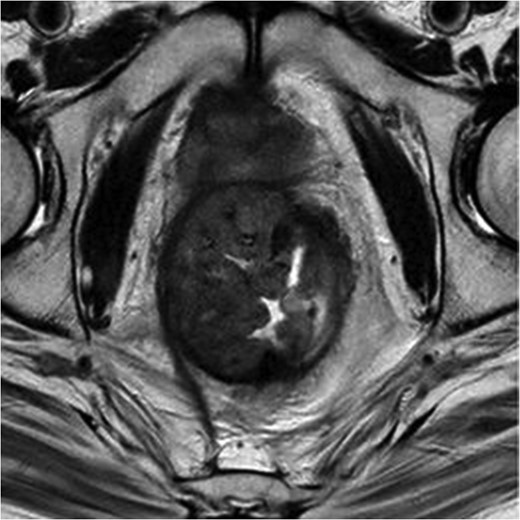

MRI pelvis. T2 waited axial image through lower pelvis through the large polypoid rectal tumour with T3 extension involving the CRM.